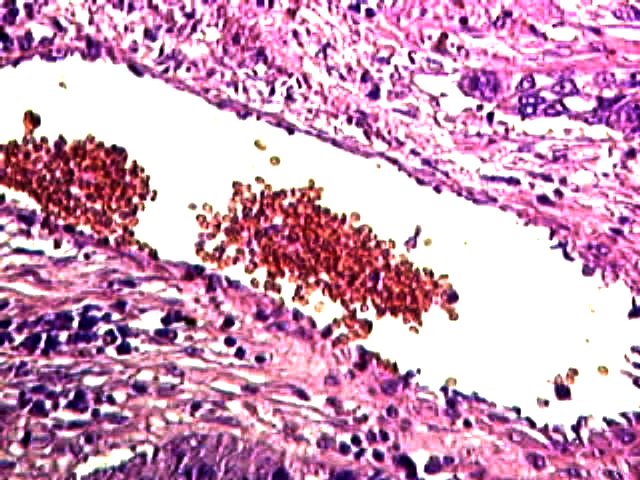

RÉSULTATS.

Capillaire dans une tumeur du poumon 550 X

Cancer du poumon (Tabac) 550 X

Cellule cancéreuse agrandie 2100 x

Hémalun Eosine

Leitz Orthoplan + ToUcam Pro